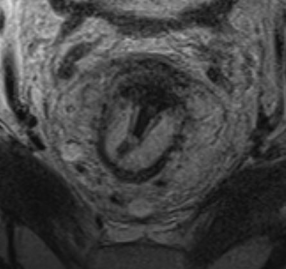

МРТ обладает высокой тканевой контрастностью, что позволяет выявлять минимальные изменения и дифференцировать опухоль от вторичных воспалительных реакций (рис. 2).

Опухоли прямой кишки характеризуются сигналом средней интенсивности на Т2-ВИ, ограничением диффузии и нарушением дифференцировки слоёв стенки кишки.

Ключевой характеристикой является наличие муцинозного компонента. Муцинозные опухоли демонстрируют высокую интенсивность сигнала на Т2-ВИ, что позволяет достоверно идентифицировать их при МРТ-исследовании (рис. 2). Несмотря на то что окончательная верификация опухоли осуществляется гистологически, МРТ обладает большей диагностической эффективностью при выявлении муцинозных образований по сравнению с биопсией (18% против 5% соответственно) [2].